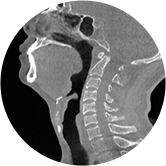

• 气道

• 颈椎

气道三维影像重建